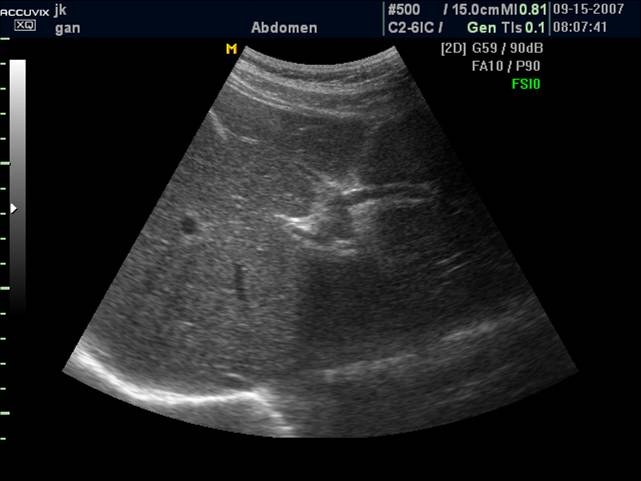

正常肝脏声像图:左图为肝右叶肋间切;右图为肝左叶剑下纵切

正常肝实质显示中等回声,光点稀疏、细微、分布均匀,肝内管道系统走行正常,纹理清晰。

肝包膜因含有纤维结缔组织, 肝膈面包膜光滑呈纤细的强回声。肝左叶边缘锐利左下缘角在35~45°之间,右下缘稍钝圆,80°以内。肝与右肾之间有明显的强回声分界。